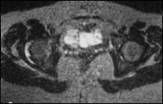

Rheumatoid arthritis

Thickened synovium

Concentric narrowing of joint